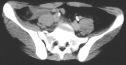

Radiographs:

Radiographs revealed a vertical buckle fracture of the right inferior sacrum, oblique fractures of the superior and inferior rami on the right and a fracture through the medial acetabulum. Obturator and iliac oblique inlet and outlet pelvic views, and a thin cut CT with 3-D reconstruction of the acetabulum were performed. These elucidated a comminuted anterior wall with fracture line extending to the posterior column. The posterior column was non-displaced. The pelvic fracture was non-displaced.

1. Right T-shaped acetabular fracture with anterior wall comminution.